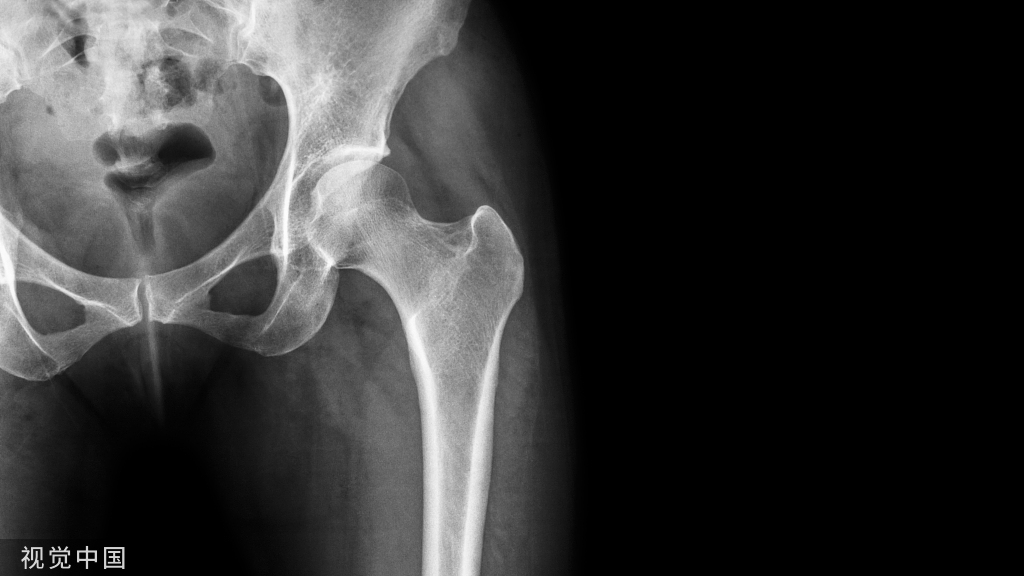

>>髋、股骨与胫骨:股骨近端骨折行DHS,医师头、甲状腺与手指,辐射量分别为0.03mSv,0.04mSv与0.12mSv;助手辐射值类似,但透视时间长于有经验外科医师;